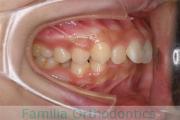

- ≫治療前

上顎

下顎

前歯の関係など

右側

正面

左側